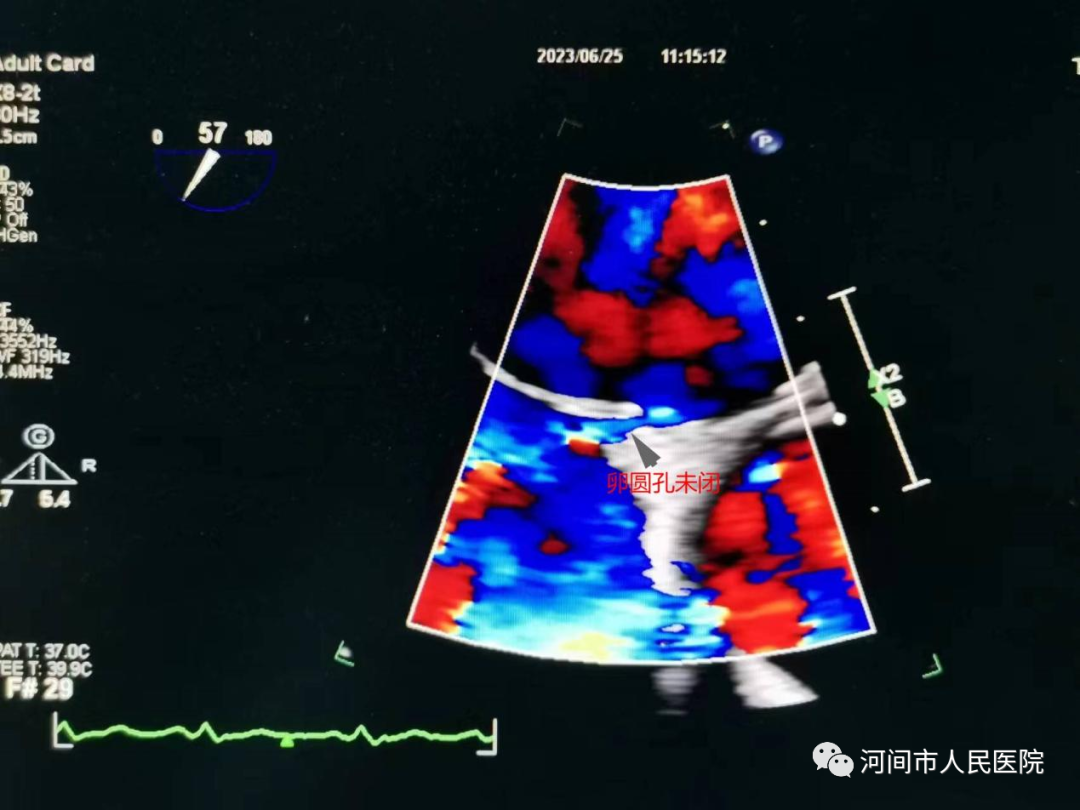

经食管超声心动图(TEE)是把超声探头放到食管内,由于探头更贴近心脏,不像经胸超声心动图那样受胸壁和肺气影响,图像显示的更清晰,特别是对左心耳等经胸超声不能看到的结构也能清晰显示。

1、偏头痛及年轻的脑卒中患者,怀疑有卵圆孔未闭的。